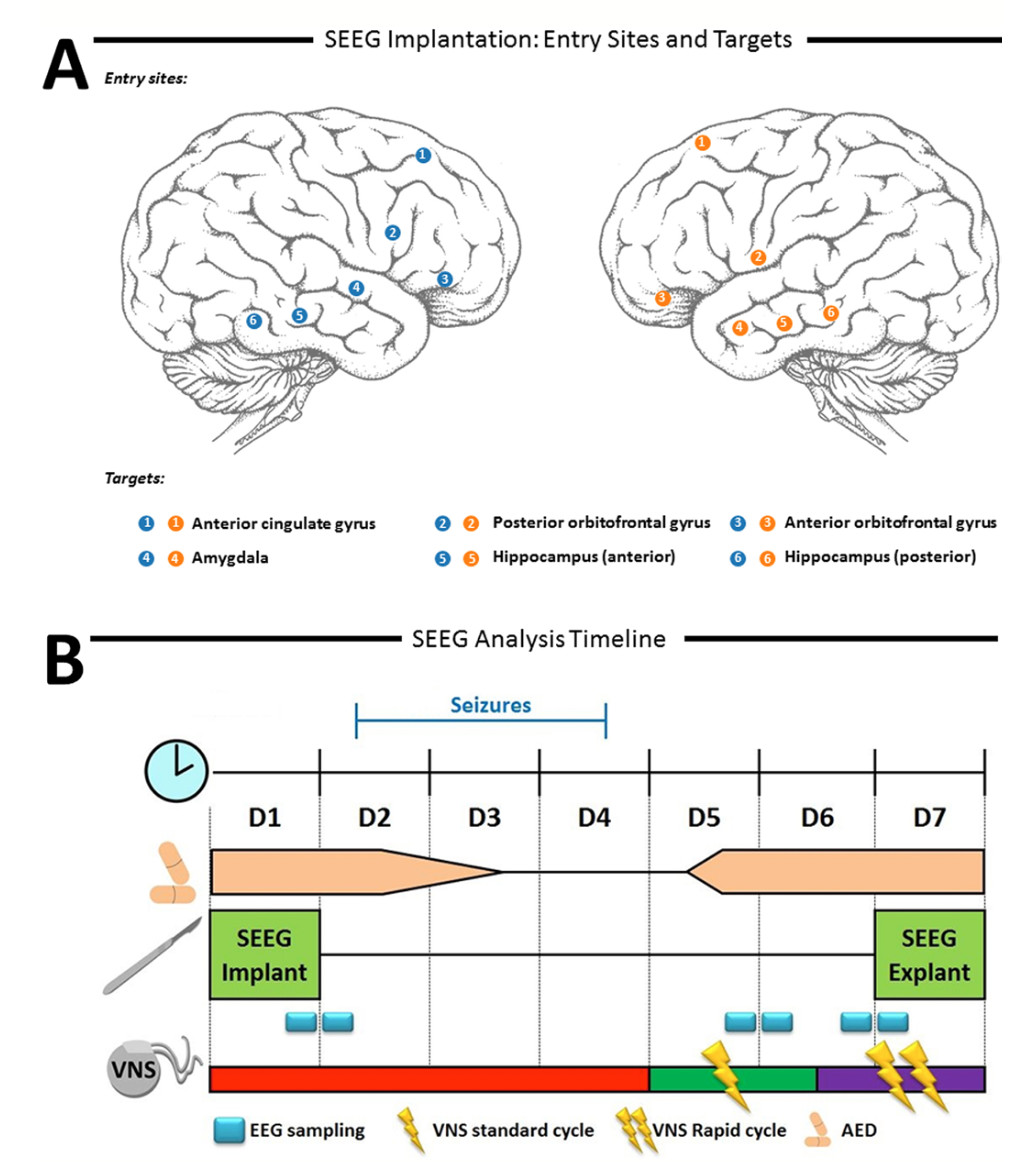

迷走神经刺激术(VNS)治疗难治性癫痫的机制,可能是海马和丘脑皮质回路的去同步化,但是,关于剂量-反应关系和时间动态的具体机制了解甚少。在非癫痫大鼠模型中的研究结果表明,快速周期(RC)VNS比标准周期(SC)VNS具有更好的去同步化效果。作者首次在人体中,报告了在创伤后双侧中颞叶-颞叶癫痫病(药物和SC-VNS耐受)患者中VNS的神经调控剂量-反应关系。在立体定向脑电图(SEEG)记录期间,VNS先处于关闭状态(off-set),改为SC-VNS,再改为RC-VNS设置。频谱分析显示,与off-set相比,SC-和RC-VNS的theta(4-8Hz)和alpha(8-15Hz)频段的功率总体降低(p<0.001)。在α波段,与off-set相比,SC-和RC-VNS都有较明显的全局去同步化(p<0.001)。在双侧海马体中,RC-VNS与SC-VNS相比,光谱功率进一步降低(p<0.001)。剂量-反应和时间效应表明,VNS对区域和全局动力学的调控作用不同。

图:试验流程图。